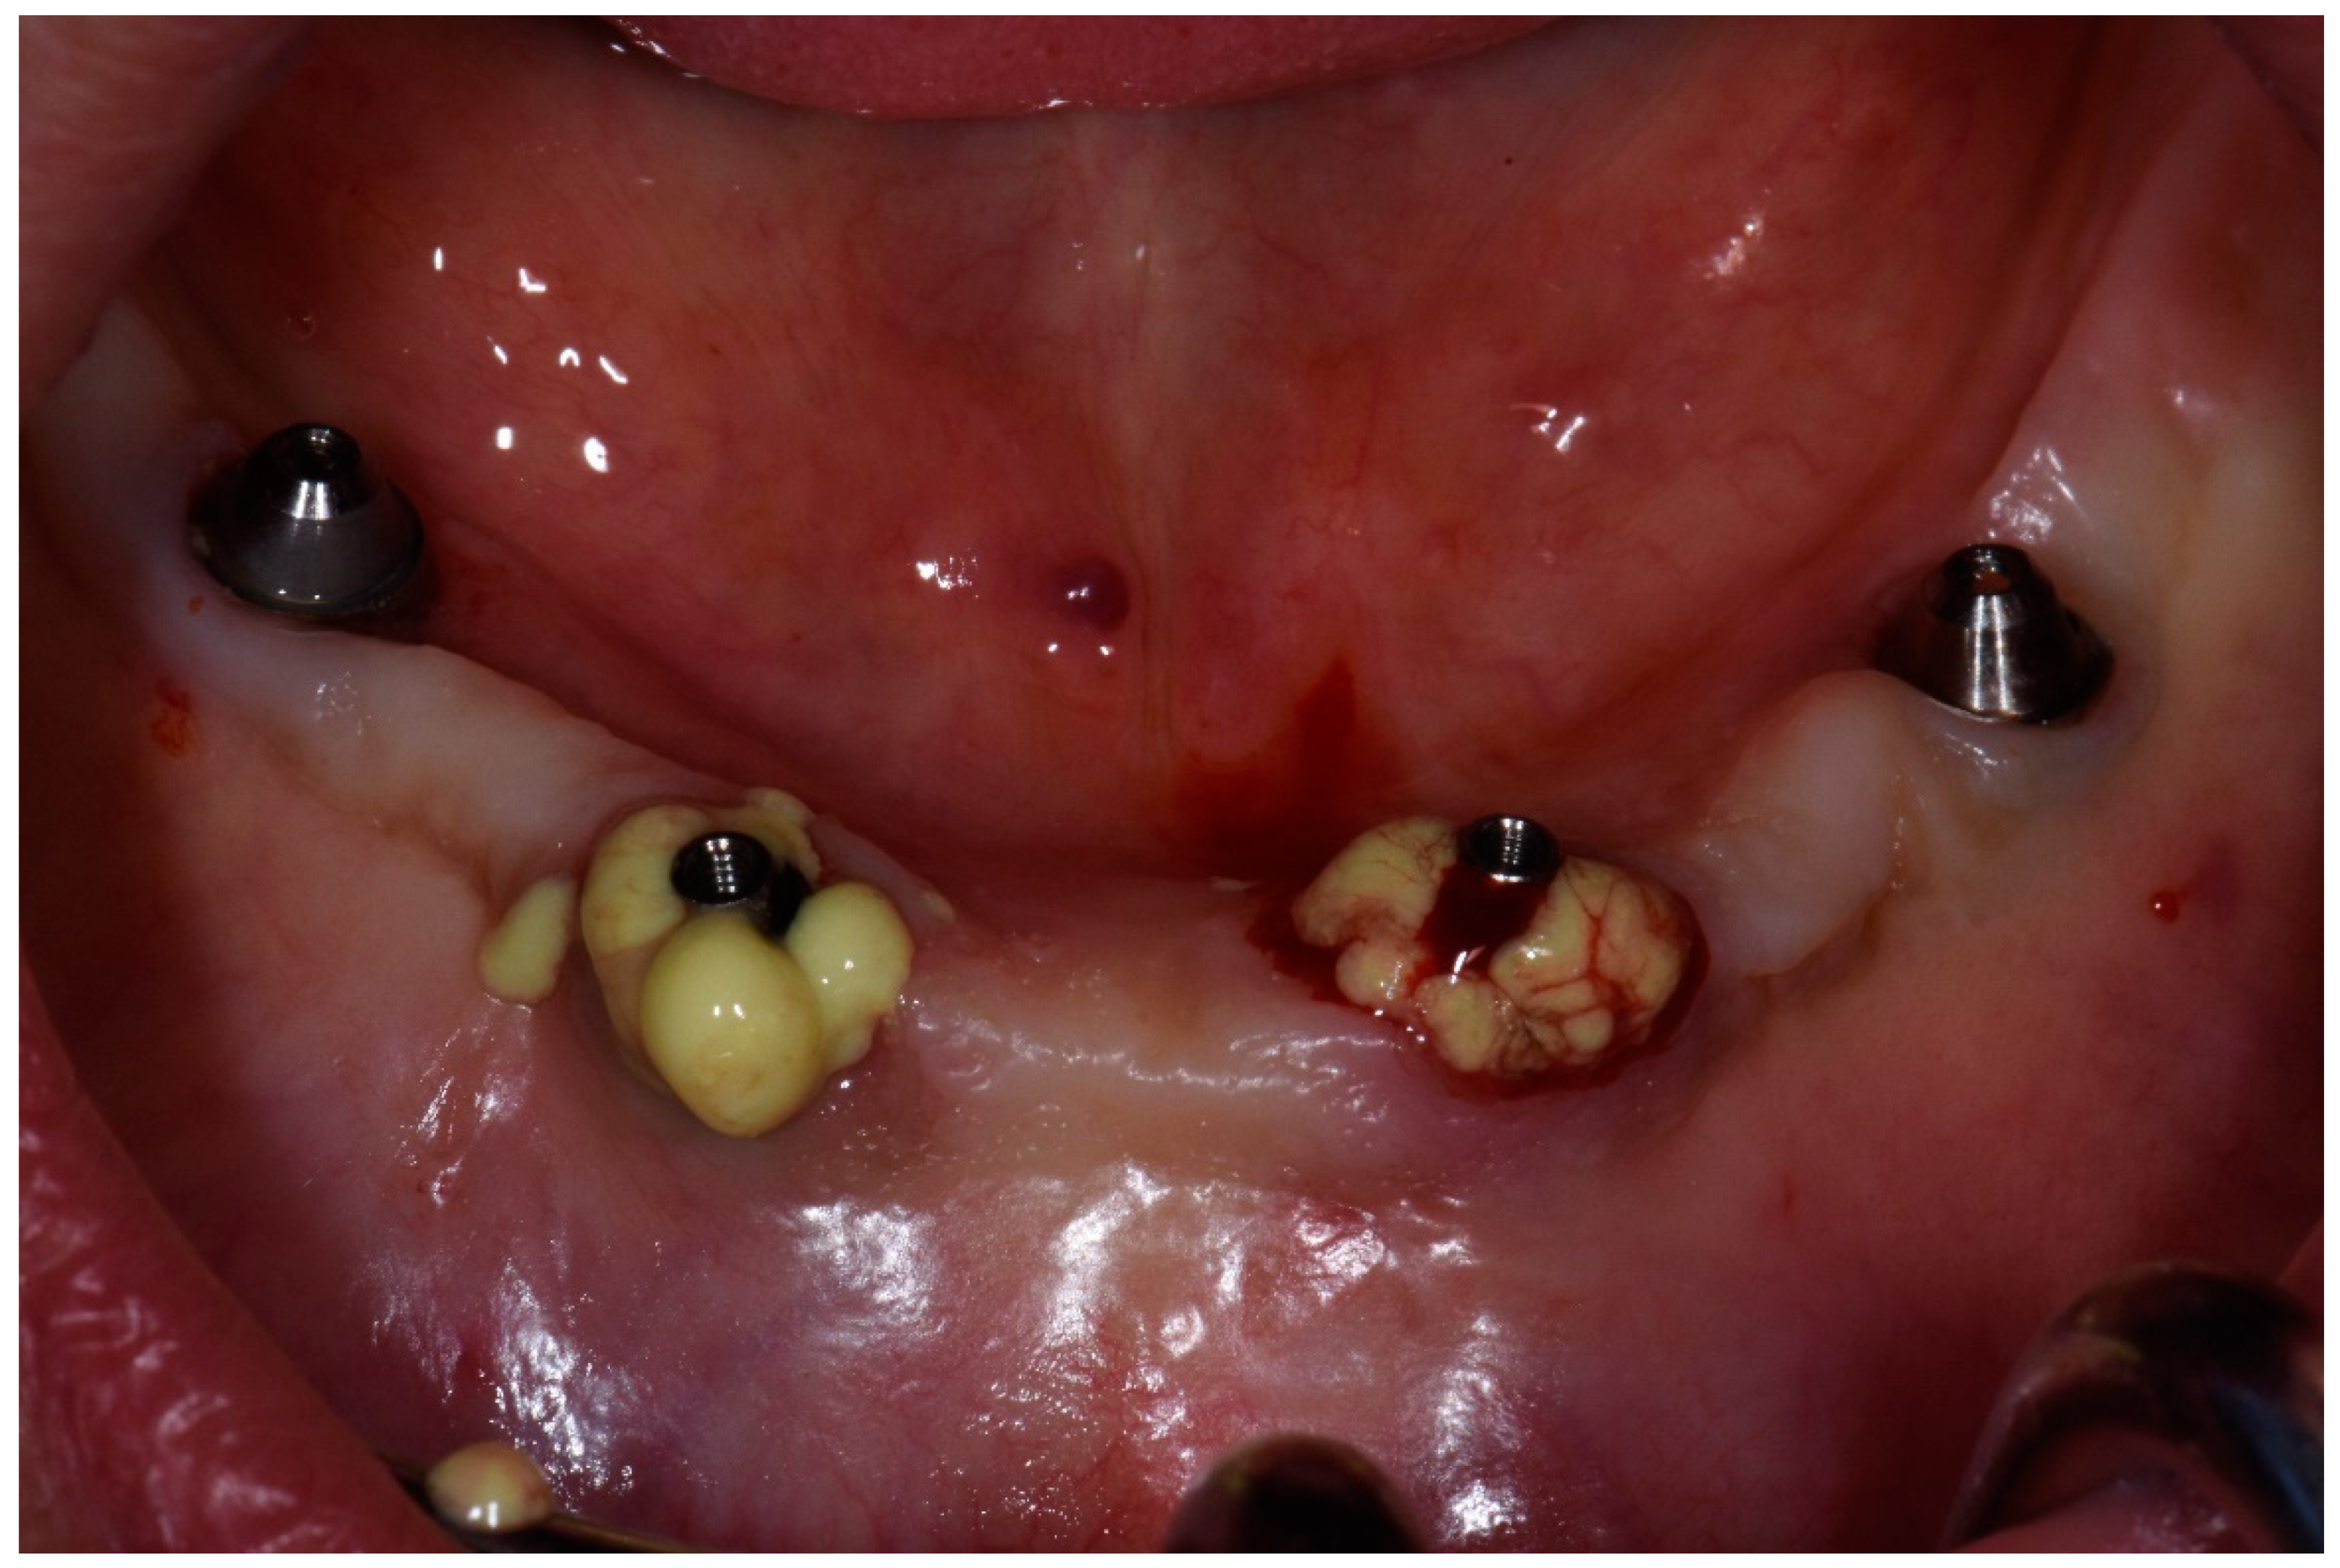

Figure 12.

Condition of peri-implant tissues in patient in 6 months after treatment.

Bidimensional radiographic assessment of the lower jaw implants (with periapical and panoramic radiograph) was done. In the lower jaw, a concave bone resorption of about 2.5 mm mesial and distal to both distal implants were observed, and there was no bone resorption in two central implants (Figure 13 and Figure 14).